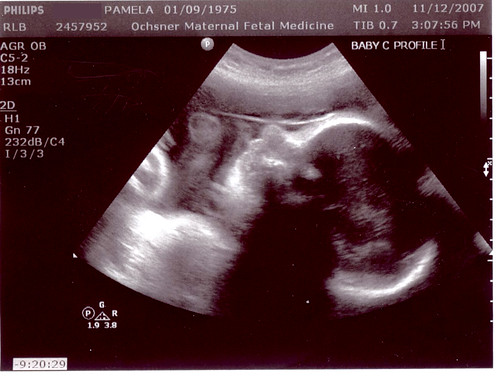

Oh, pics? Want to see them? C was being uncooperative, so we only have A & B. But like it matters – they basically look all the same anyway. 😛